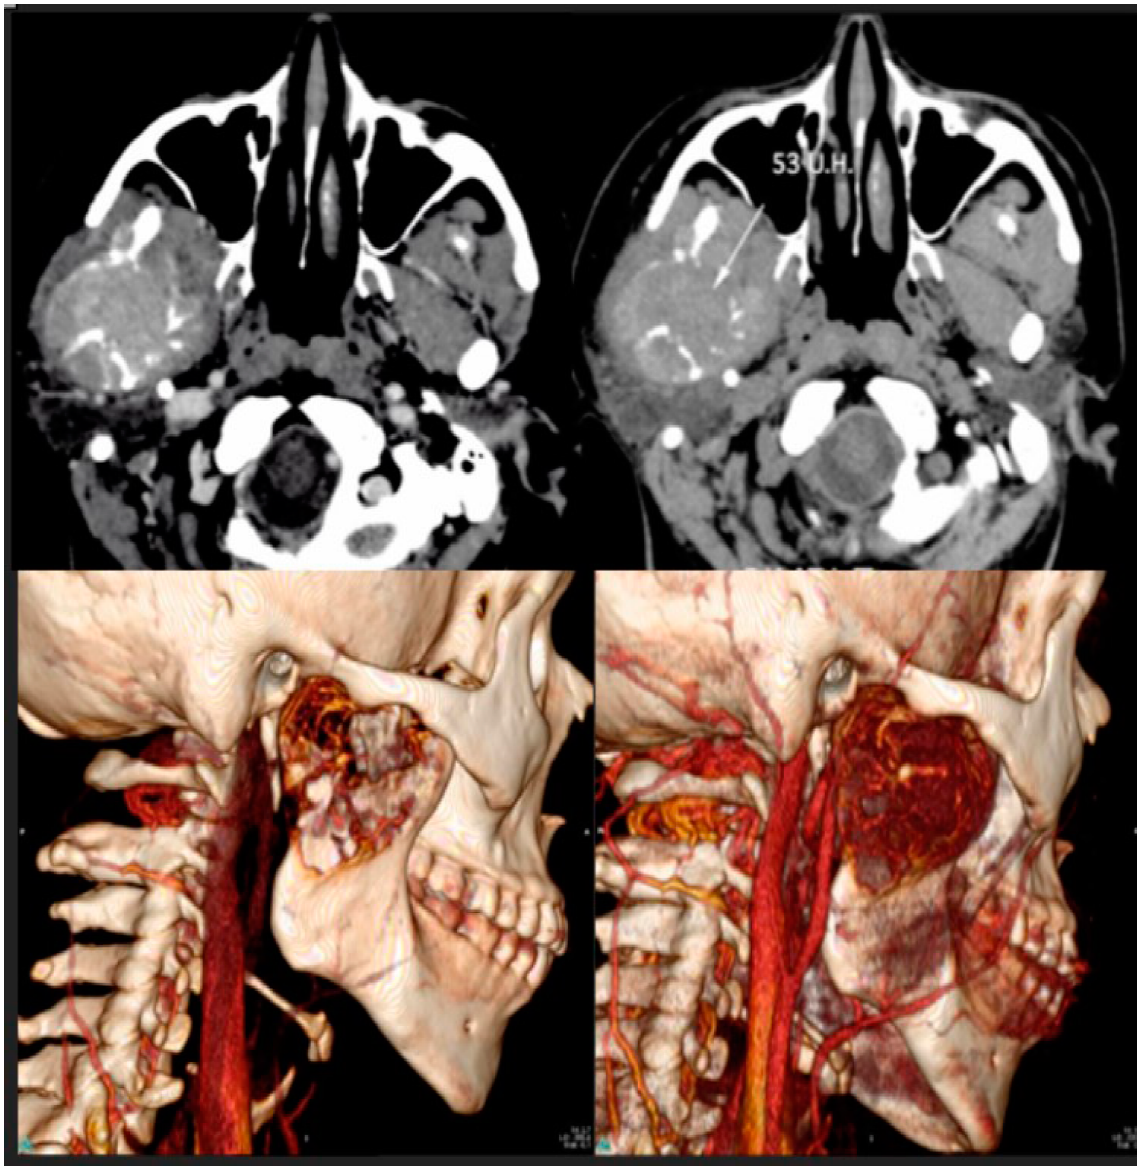

La reconstrucción multiplanar de la tomografía computarizada (TC) y la reconstrucción tridimensional de la imagen, muestran un tumor óseo expansivo con componente de partes blandas, con una densidad media de 53 unidades Hounsfield (UH), evidencia homogénea tras la administración de contraste intravenoso, pérdida del plano graso de los elementos adyacentes al pterigoideo, de los músculos maseteros y del borde anterior de la infiltración de la glándula parótida. El tumor destruye la rama ascendente, el cóndilo mandibular y la escotadura mandibular (Figura 1). No había evidencia clínica ni radiológica de adenopatías cervicales. El examen histológico (Figura 2. A-F) mostró láminas e islas de epitelio odontogénico que contenían numerosas células fantasma que mostraban calcificación focal. Sobre la base de estos hallazgos, el tumor se diagnosticó como un carcinoma odontogénico de células fantasma. La paciente fue sometida a una escisión total y a una reconstrucción intraoperatoria mandibular inmediata. El postoperatorio transcurrió sin incidentes y no se recomendó radioterapia adyuvante.

Figura 1 Imágenes tomográficas de Carcinoma Odontogénico de Células Fantasma en el Maxilar. Arriba: corte axial. Abajo: Reconstrucción 3D.